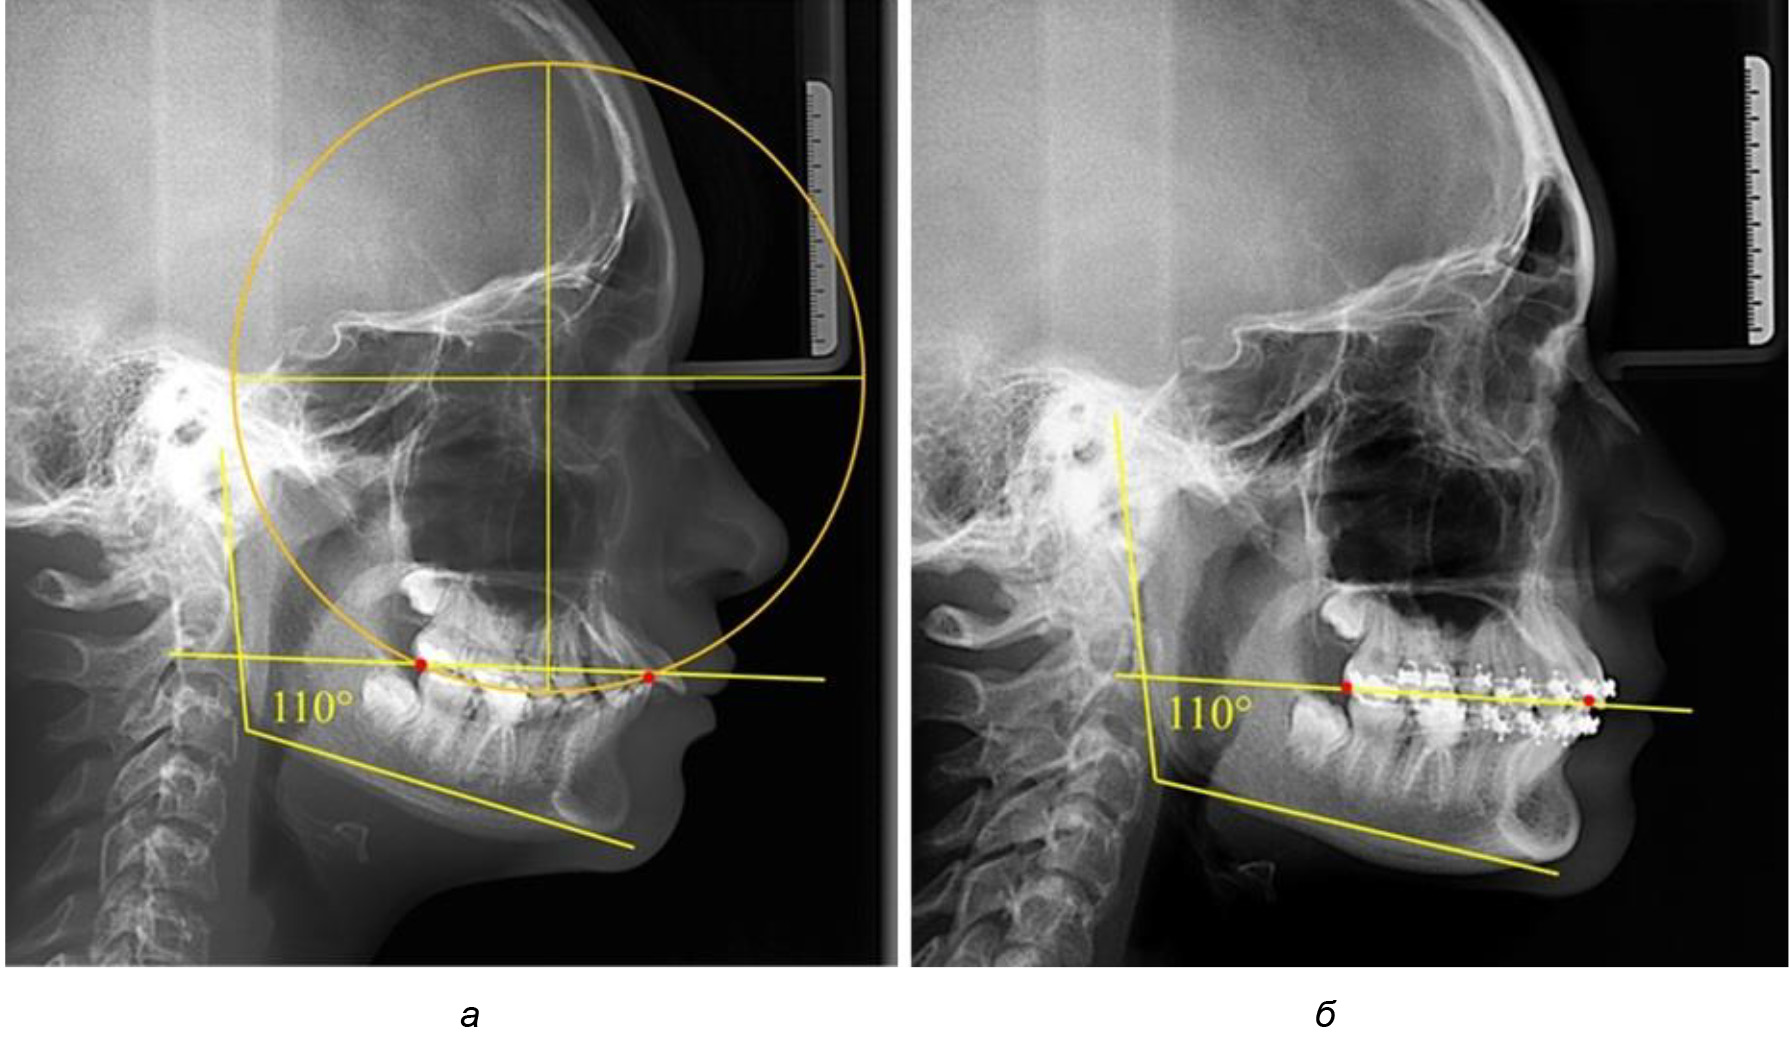

В 3-ю подгруппу вошли ТРГ и ОПТГ 14 человек 1-й группы, что составило (22,58 ± 5,31) % от общего количества людей 1-й группы. Величина угла нижней челюсти в среднем составила (114,85 ± 2,87)° и характеризовала горизонтальный тип нижней челюсти.

Глубина кривой Spee в среднем по 2-й подгруппе составил (2,94 ± 0,47) мм, что было меньше, чем в других подгруппах. Деление величины радиуса круга к длине окклюзионной линии составило 1,616 ± 0,02 (рис. 4).

Рис. 4. Особенности кривой Spee на ТРГ (а) и ОПТГ (б) у людей с горизонтальным типом лица